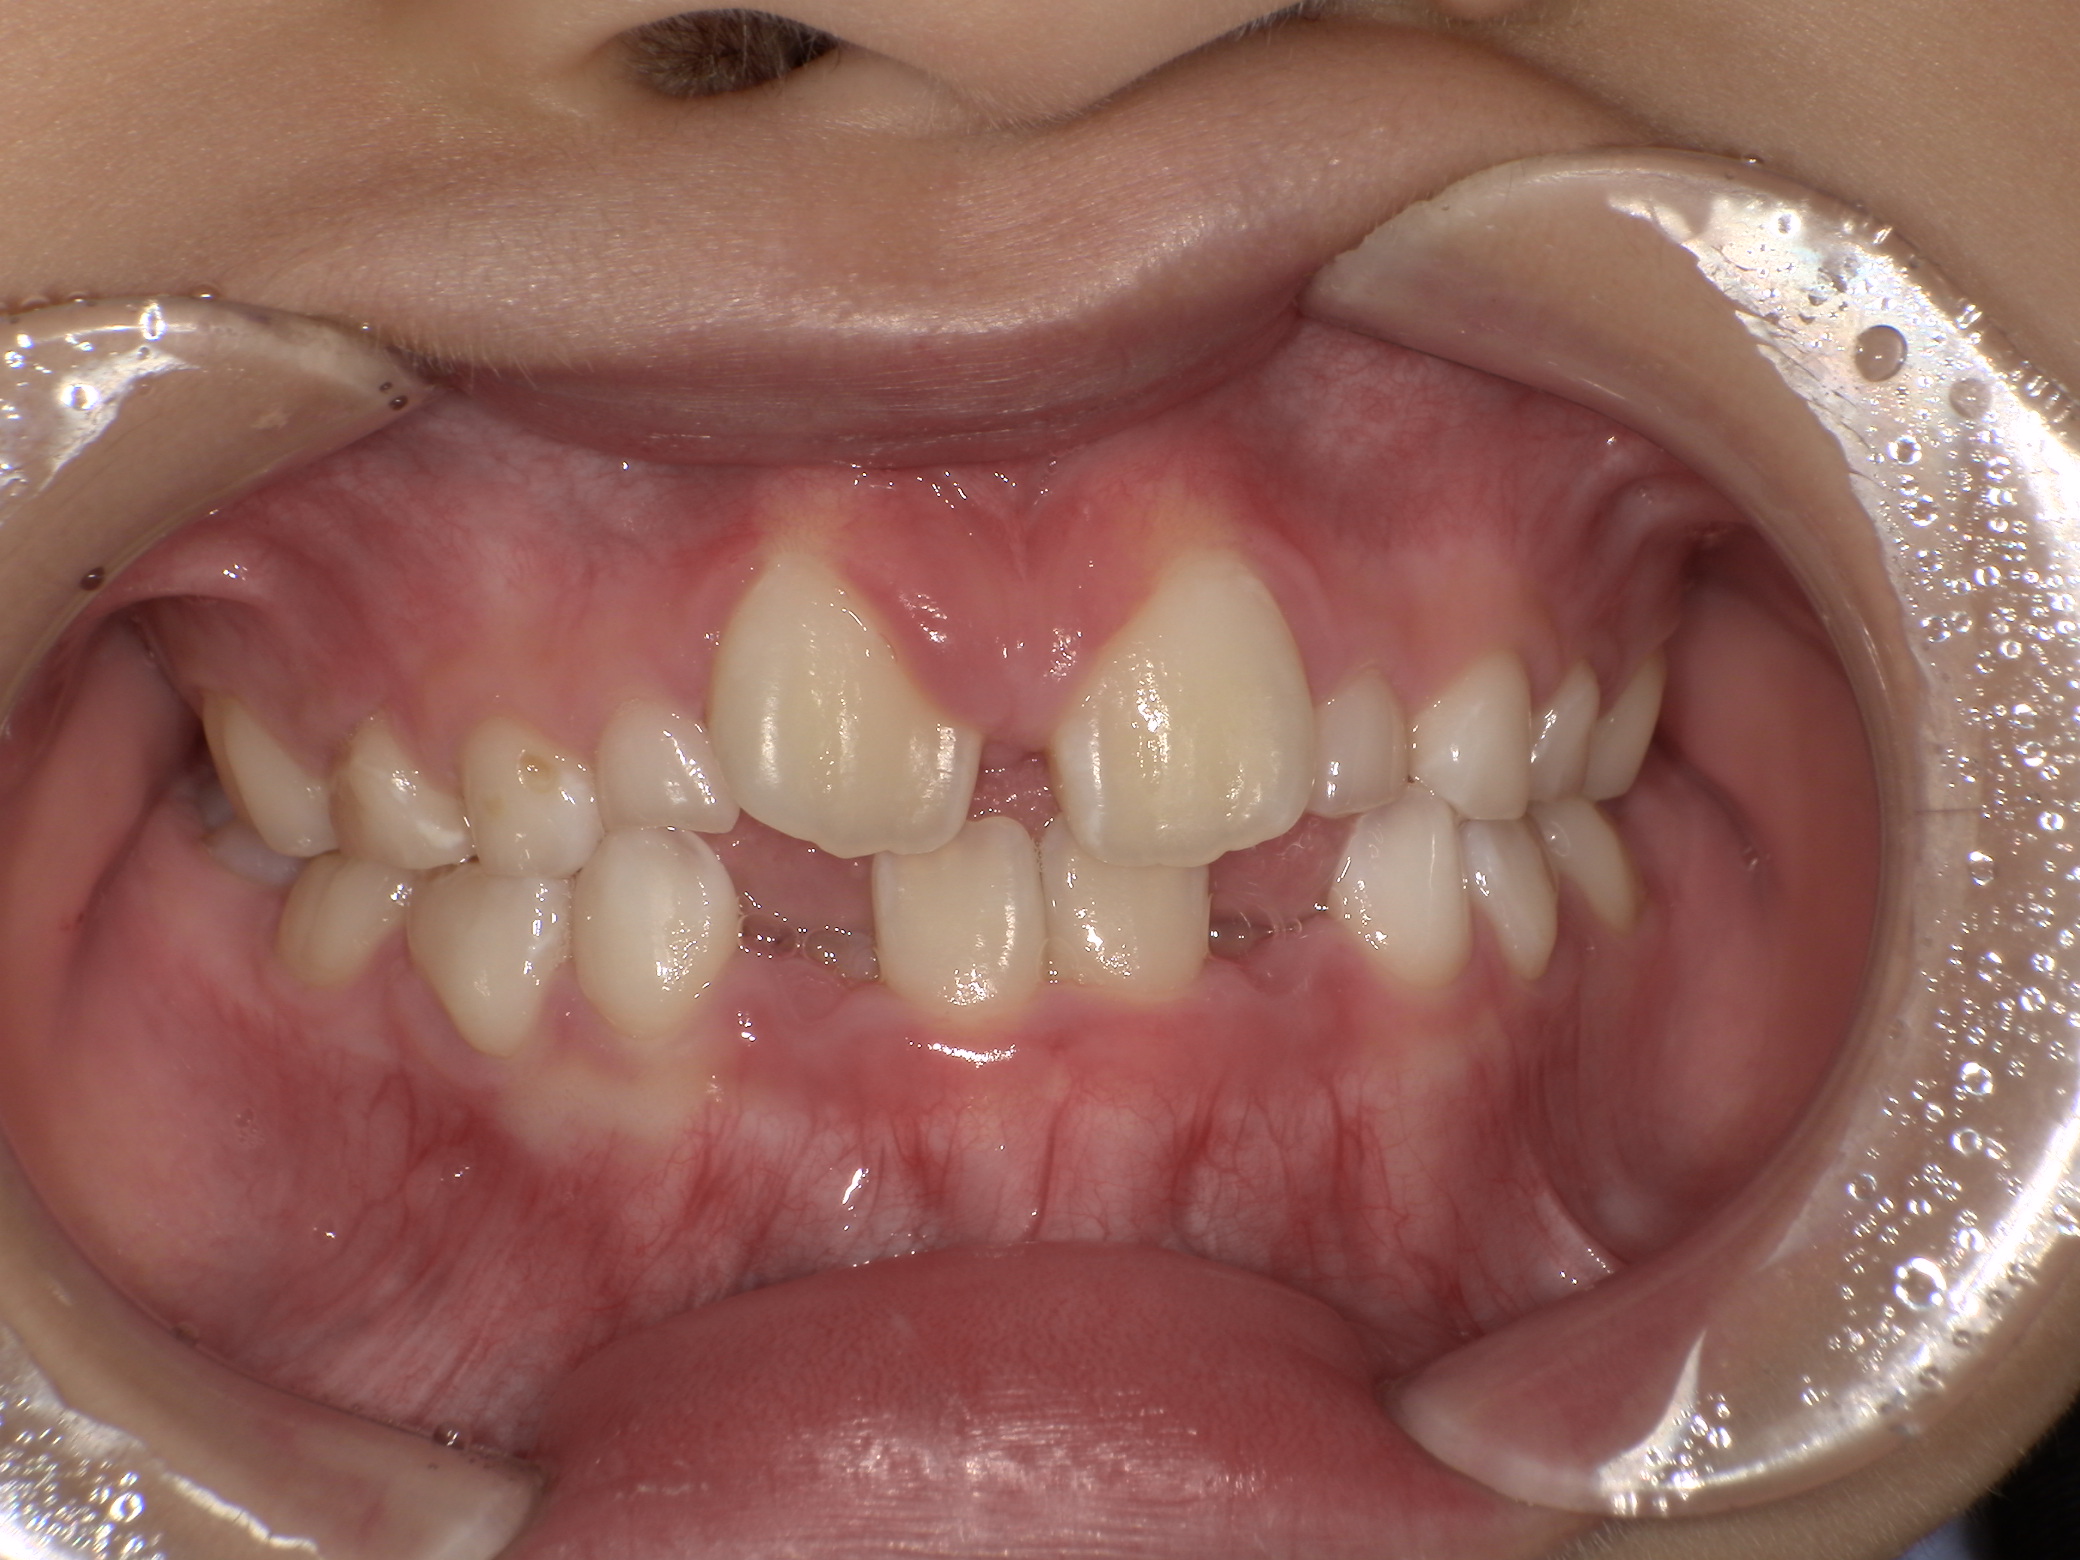

上写真:治療開始前(5歳2か月)

上の前歯が見えないくらいに下の前歯が出ていました。